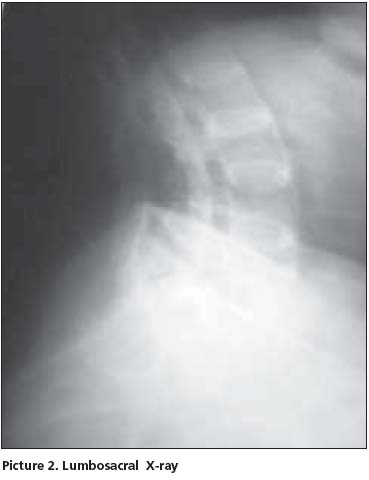

Her postero-anterior chest x-ray was evaluated as normal. In thoracic (Picture 1) and lumbosacral (Picture 2) graphs, marked squaring in her vertebras, shiny corners, symmetric syndesmophytes, bamboo spine, trolley track sign, osteoporosis and left faced scoliosis were observed. In pelvic x-ray her sacroiliac joints were normal. There were enthesopathic changes in the localization of the insertion of achilles tendon in calcaneus posterior bilaterally (picture 3). In magnetic resonance imaging (MRI) and conventional radiography, bilateral sacroiliac joints were regular and joints cartilage were normal (Picture 4,5). There were not any pathological signal changes in the bone surfaces that form the joints and the soft structures that were examined. Depending on the current clinical status and the radiography and imaging tests, the patient was defined as spondyloarthropathy (SpA).